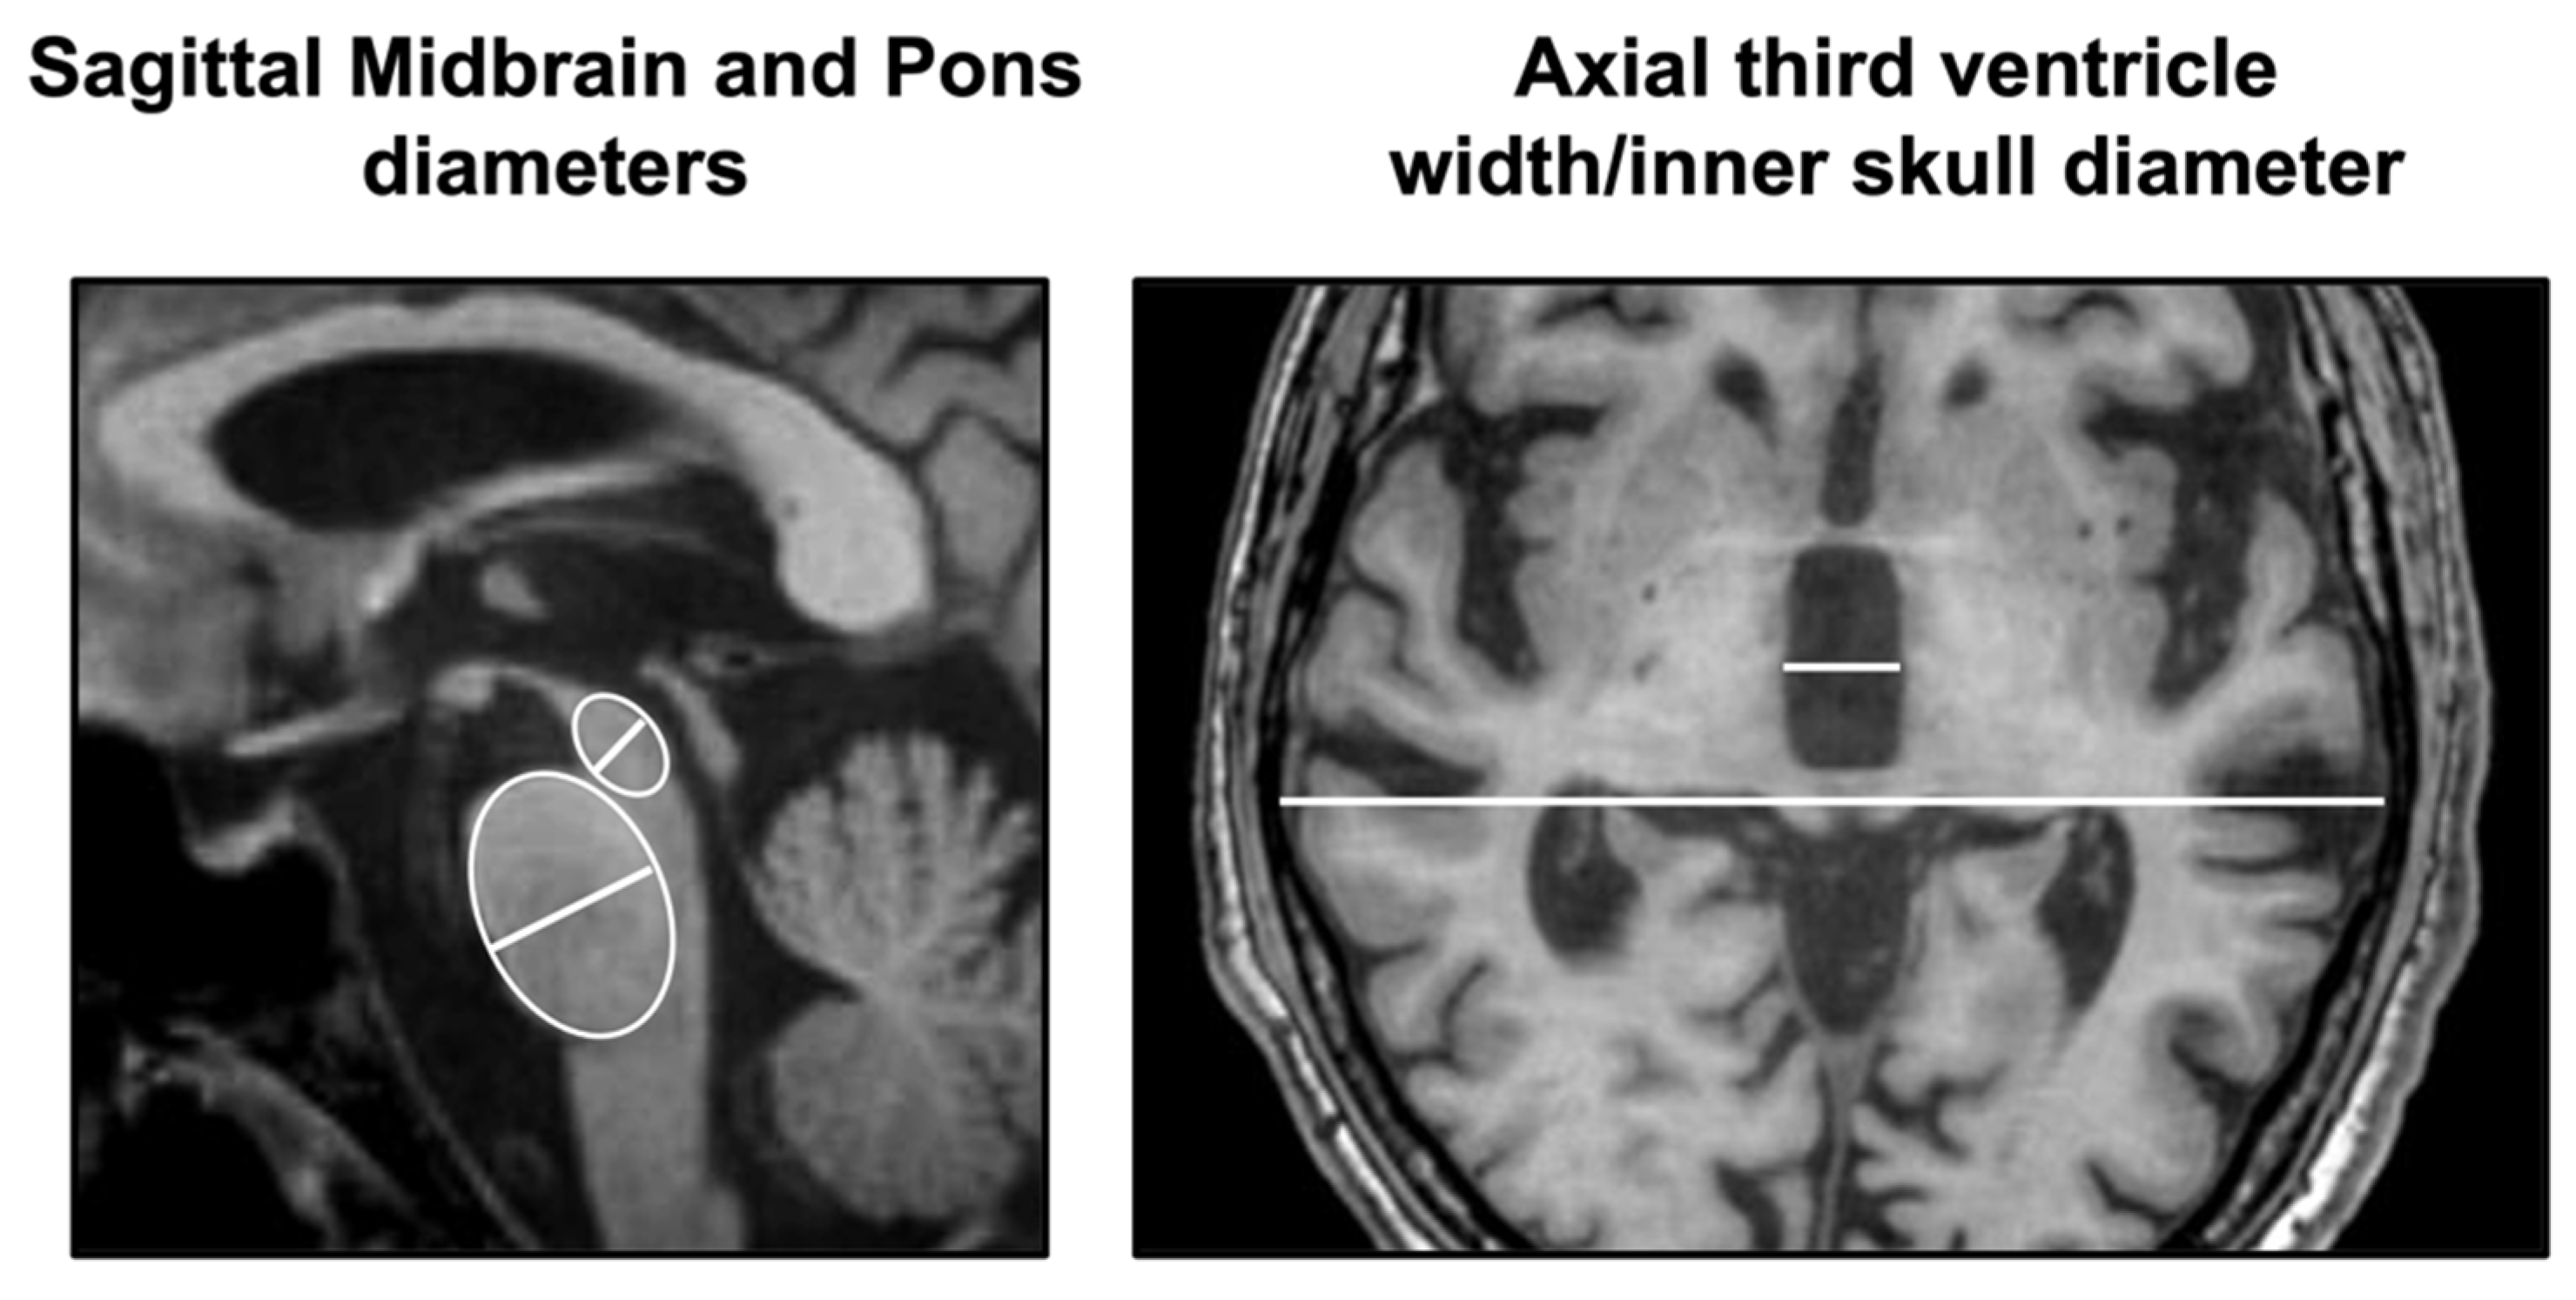

2.1. Simple Manual Linear Measurements

2.2. Simple Manual Non-Linear Measurements

2.3. Combined MR Planimetric Biomarkers